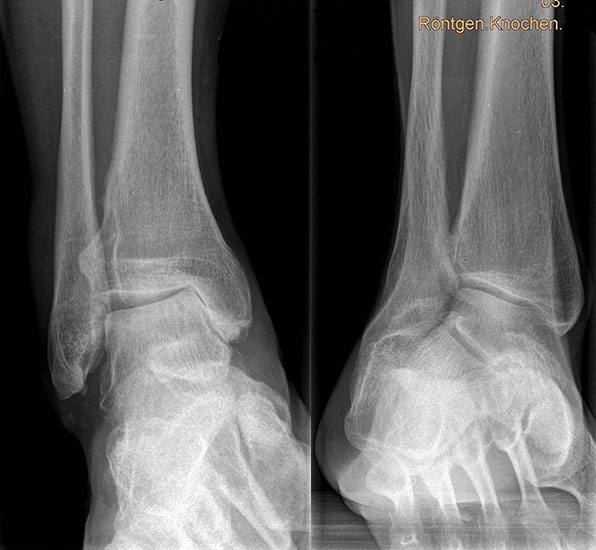

Auf dem linken Bild (a) Varusarthrose des oberen Sprunggelenks mit deutlicher Mehrbelastung der medialen Gelenkanteile. Dort bereits deutlich sichtbarer Knorpelverlust. Rechtes Bild (b) Valgusarthrose des oberen Sprunggelenks. Erhöhte Druckbelastung in de

Abbildung 1